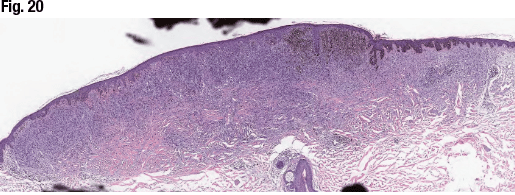

Another case—a 69-year-old with a pigmented lesion on the left scapula—had a diagnosis of blue nevus-like melanoma arising in association with blue nevus (Figs. 20–22). MART-1/Ki67 showed high proliferative rate in large epithelioid melanocytes and low to absent proliferative rate in spindle-shaped melanocytes. HMB-45 showed diffuse expression in epithelioid and spindle cells.

“The best diagnosis for this case is blue nevus-like melanoma arising in association with blue nevus due to the presence of irregular pigmentation, asymmetry, infiltrative border, biphenotypic features, cytologic atypia, atypical mitotic figures, and high proliferative rate,” Dr. Aung said. “And the patient’s sentinel lymph node also showed positive metastatic melanoma highlighted with pan-melanoma cocktail.”